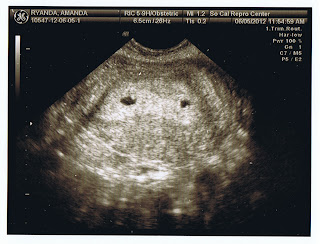

We posted this 12 week ultra sound image on facebook and got a great response. Someone referred to the babies as "The Twyndas" and that's how we got the name of this blog.

The Proof!

A couple very long weeks after the embryo transfer, we received a phone call from one of our nurses. She had HAPPY news to share! Hard work, modern medical miracles, and some plain old good luck paid off. She said, "Congratulations! Amanda's pregnant" She also told us that Amanda's hormone levels were on the high end. We asked if this could mean a multiple pregnancy and she told us we would need to come in for an ultra sound. Here's what we saw...